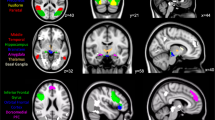

Regions of interest

FreeSurfer (version 6.0, http://surfer.nmr.mgh.harvard.edu/)46 was used to delineate brain regions on the T1-weighted MRIs. We tested two regions of interest: (i) median raphe nuclei, and (ii) a composite region consisting of anatomical structures where the [11C]MADAM signal-to-noise ratio was deemed acceptable: amygdala, anterior cingulate gyrus (ACC), posterior cingulate gyrus (PCC), caudate, hippocampus, insular cortex, putamen, and thalamus. The composite region was created using weighted standardization, with weights derived from the volume and variance in BPND for each of the included ROIs (see Supplement 1 for details).

ROIs preferentially sampling the dorsal- and median raphe respectively were created using a version of a previously described semi-automatic method44,49, here fully automated (Fig. 2, see Supplement 1 for details). For each individual, the resulting masks were applied to the WAPI-images to calculate a BPND value.

(1) FreeSurfer Brainstem Substructures. (2) The pons mask (green) was trimmed, keeping the most dorsal 5 voxels. (3) The resulting mask was overlaid on the time-weighted summated PET-image. (4) Median raphe is the structure with highest [11C]MADAM binding within the boundaries of the trimmed pons mask; the most intense PET-voxel was located and in an iterative process the voxel with highest intensity adjacent to the initial voxel was added until 65 voxels were collected. (5) The resulting mask overlaid on the MR-image. The same procedure was used to delineate a region preferentially sampling dorsal raphe except for using the midbrain mask (yellow in panel 1) and 116 voxels.

In A MADRS-S measurements during the course of ICBT. Each cell represents one patient, (n = 17), letters in lower left corner corresponds to the letters in Fig. 1, numbers in parenthesis is CGI-I. In B longitudinal [11C]MADAM data (n = 16) for the composite region, PET1 (baseline) and PET2 (after treatment). Right panel shows difference scores between scans. In C mean parametric image of patients at baseline (upper image) and after treatment (lower image; n = 16), see Supplement 3 for a 3D movie of the same data. In D longitudinal data, median raphe, BPND at PET1 (baseline, left) and PET2 (after treatment, right). In E cross-sectional data, median raphe, BPND for patients with MDD at baseline (left) and healthy controls (right). In F cross-sectional [11C]MADAM data (n = 17 + 17) for the composite region, comparing patients with MDD at baseline to matched healthy controls. Right panel shows difference scores between matched pairs.

BPND increased on average 10% in the composite region following ICBT; PET 1 Mean Z-score = −0.22 ± 0.68, PET2 Mean Z-score = 0.28 ± 0.89, t(15) = −3.01, p = 0.01, 95% CI [−0.85, −0.15], Dz = 0.75. Binding in median raphe showed no change following treatment; PET 1 Mean BPND = 2.81 ± 0.48, PET2 Mean BPND = 2.89 ± 0.53, t(15) = −0.67, p = 0.51, 95% CI [−0.31, 0.16], Dz = 0.17 (Fig. 3B–D, Supplement 3 for a 3D movie).

There was no evident difference in BPND between patients at baseline and healthy controls. [11C]MADAM binding in the composite region was on average 4% lower in controls compared to patients. The average Z-score for the composite region was −0.12 ± 0.57 for controls and 0.2 ± 0.89 for patients, providing no evidence for a difference between the groups, t(16) = −2.03, p = 0.97 (one sided), 95% CI [−0.60, Inf], Dz = 0.4 (Fig. 3C). For the median raphe, the average BPND was 2.88 ± 0.47 for controls and 2.89 ± 0.49 for patients, t(16) = −0.06, p = 0.95, 95% CI [−0.31, 0.29], Dz = 0.01 (Fig. 3E, F).

Exploratory analysis

In the longitudinal data frontal cortex, parietal cortex, ACC, PCC, insula, hippocampus and thalamus show higher BPND after ICBT. In the cross-sectional data hippocampus show higher BPND in patients at baseline compared to controls (Supplement 1, Table S2 and S3).